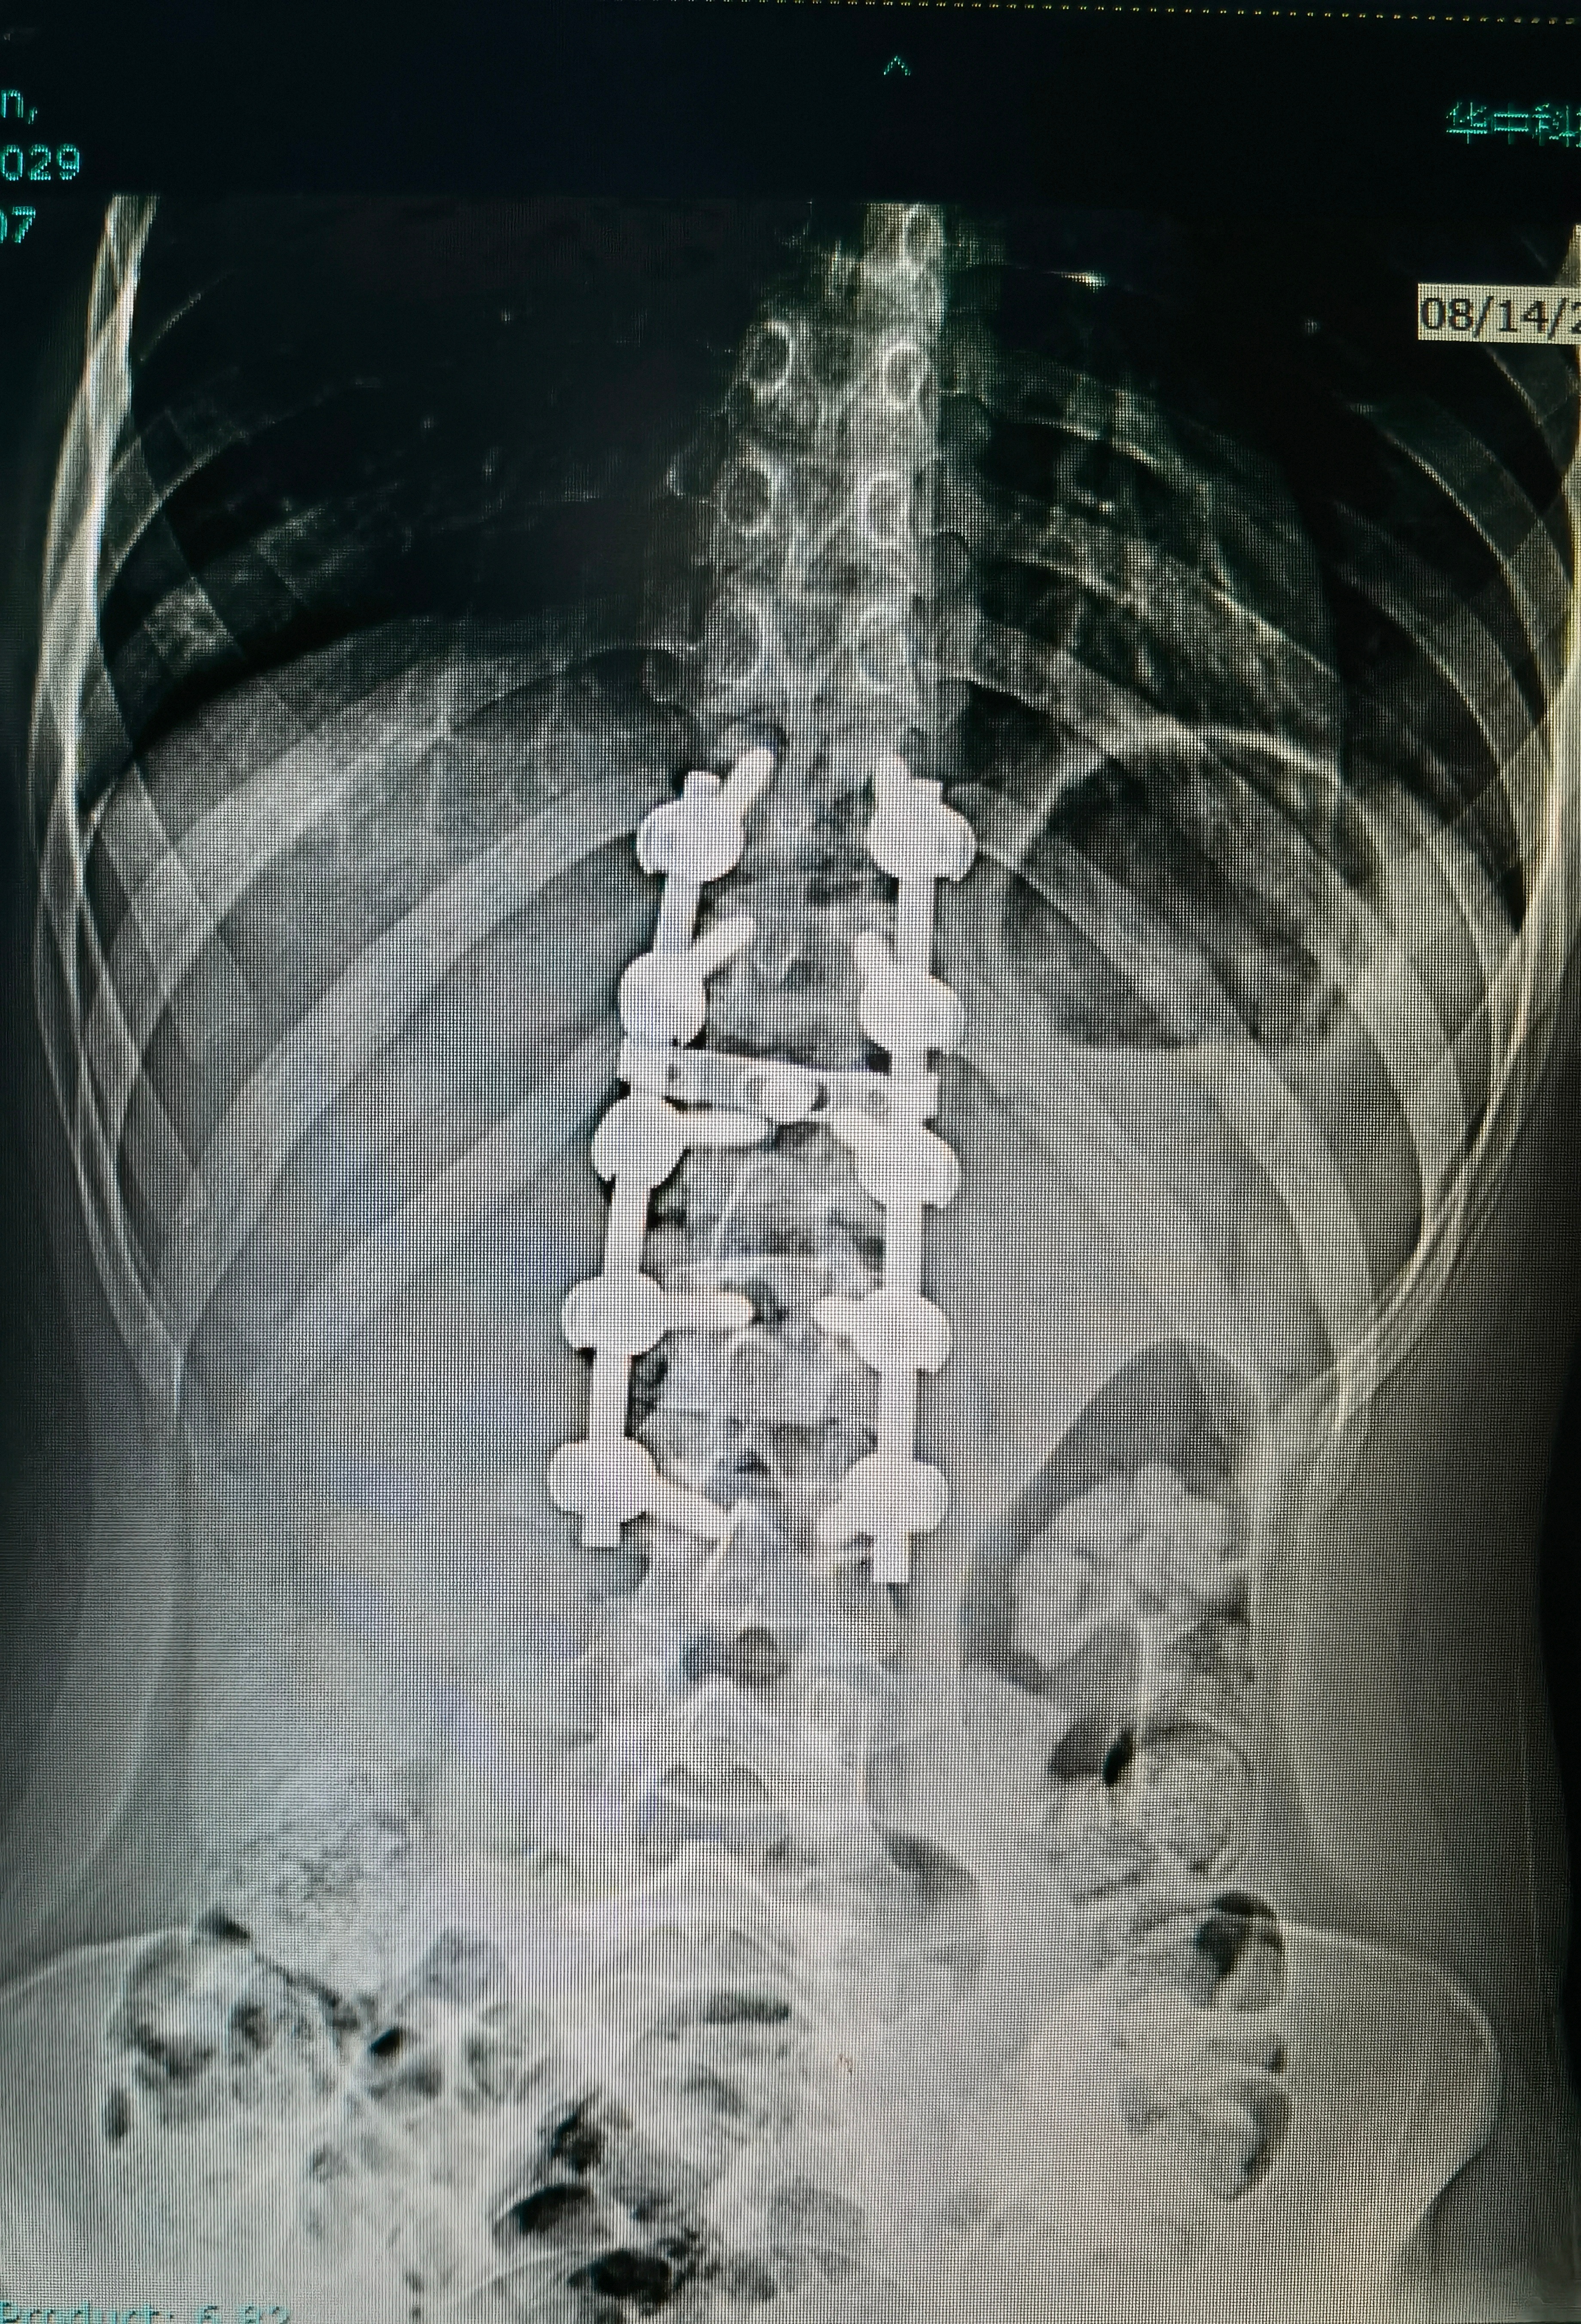

完美的手术,献给豆蔻年华的你。此刻的我,也是最幸福的[嘻嘻]

完美的手术,献给豆蔻年华的你。

此刻的我,也是最幸福的[嘻嘻]